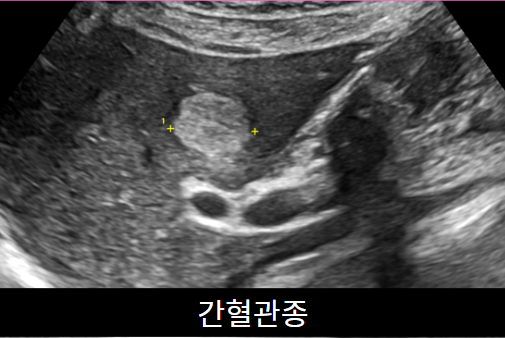

가장 많이 하는 초음파입니다. 간,담낭, 총담관, 췌장, 비장, 신장을 검사합니다. 지방간, 간경화, 간암, 혈관종, 담낭돌, 담낭용종, 췌장염 등을 진단할 수 있습니다.  약 10분 정도 소요되며 다른 검사와 달리 8시간의 공복이 필요합니다.